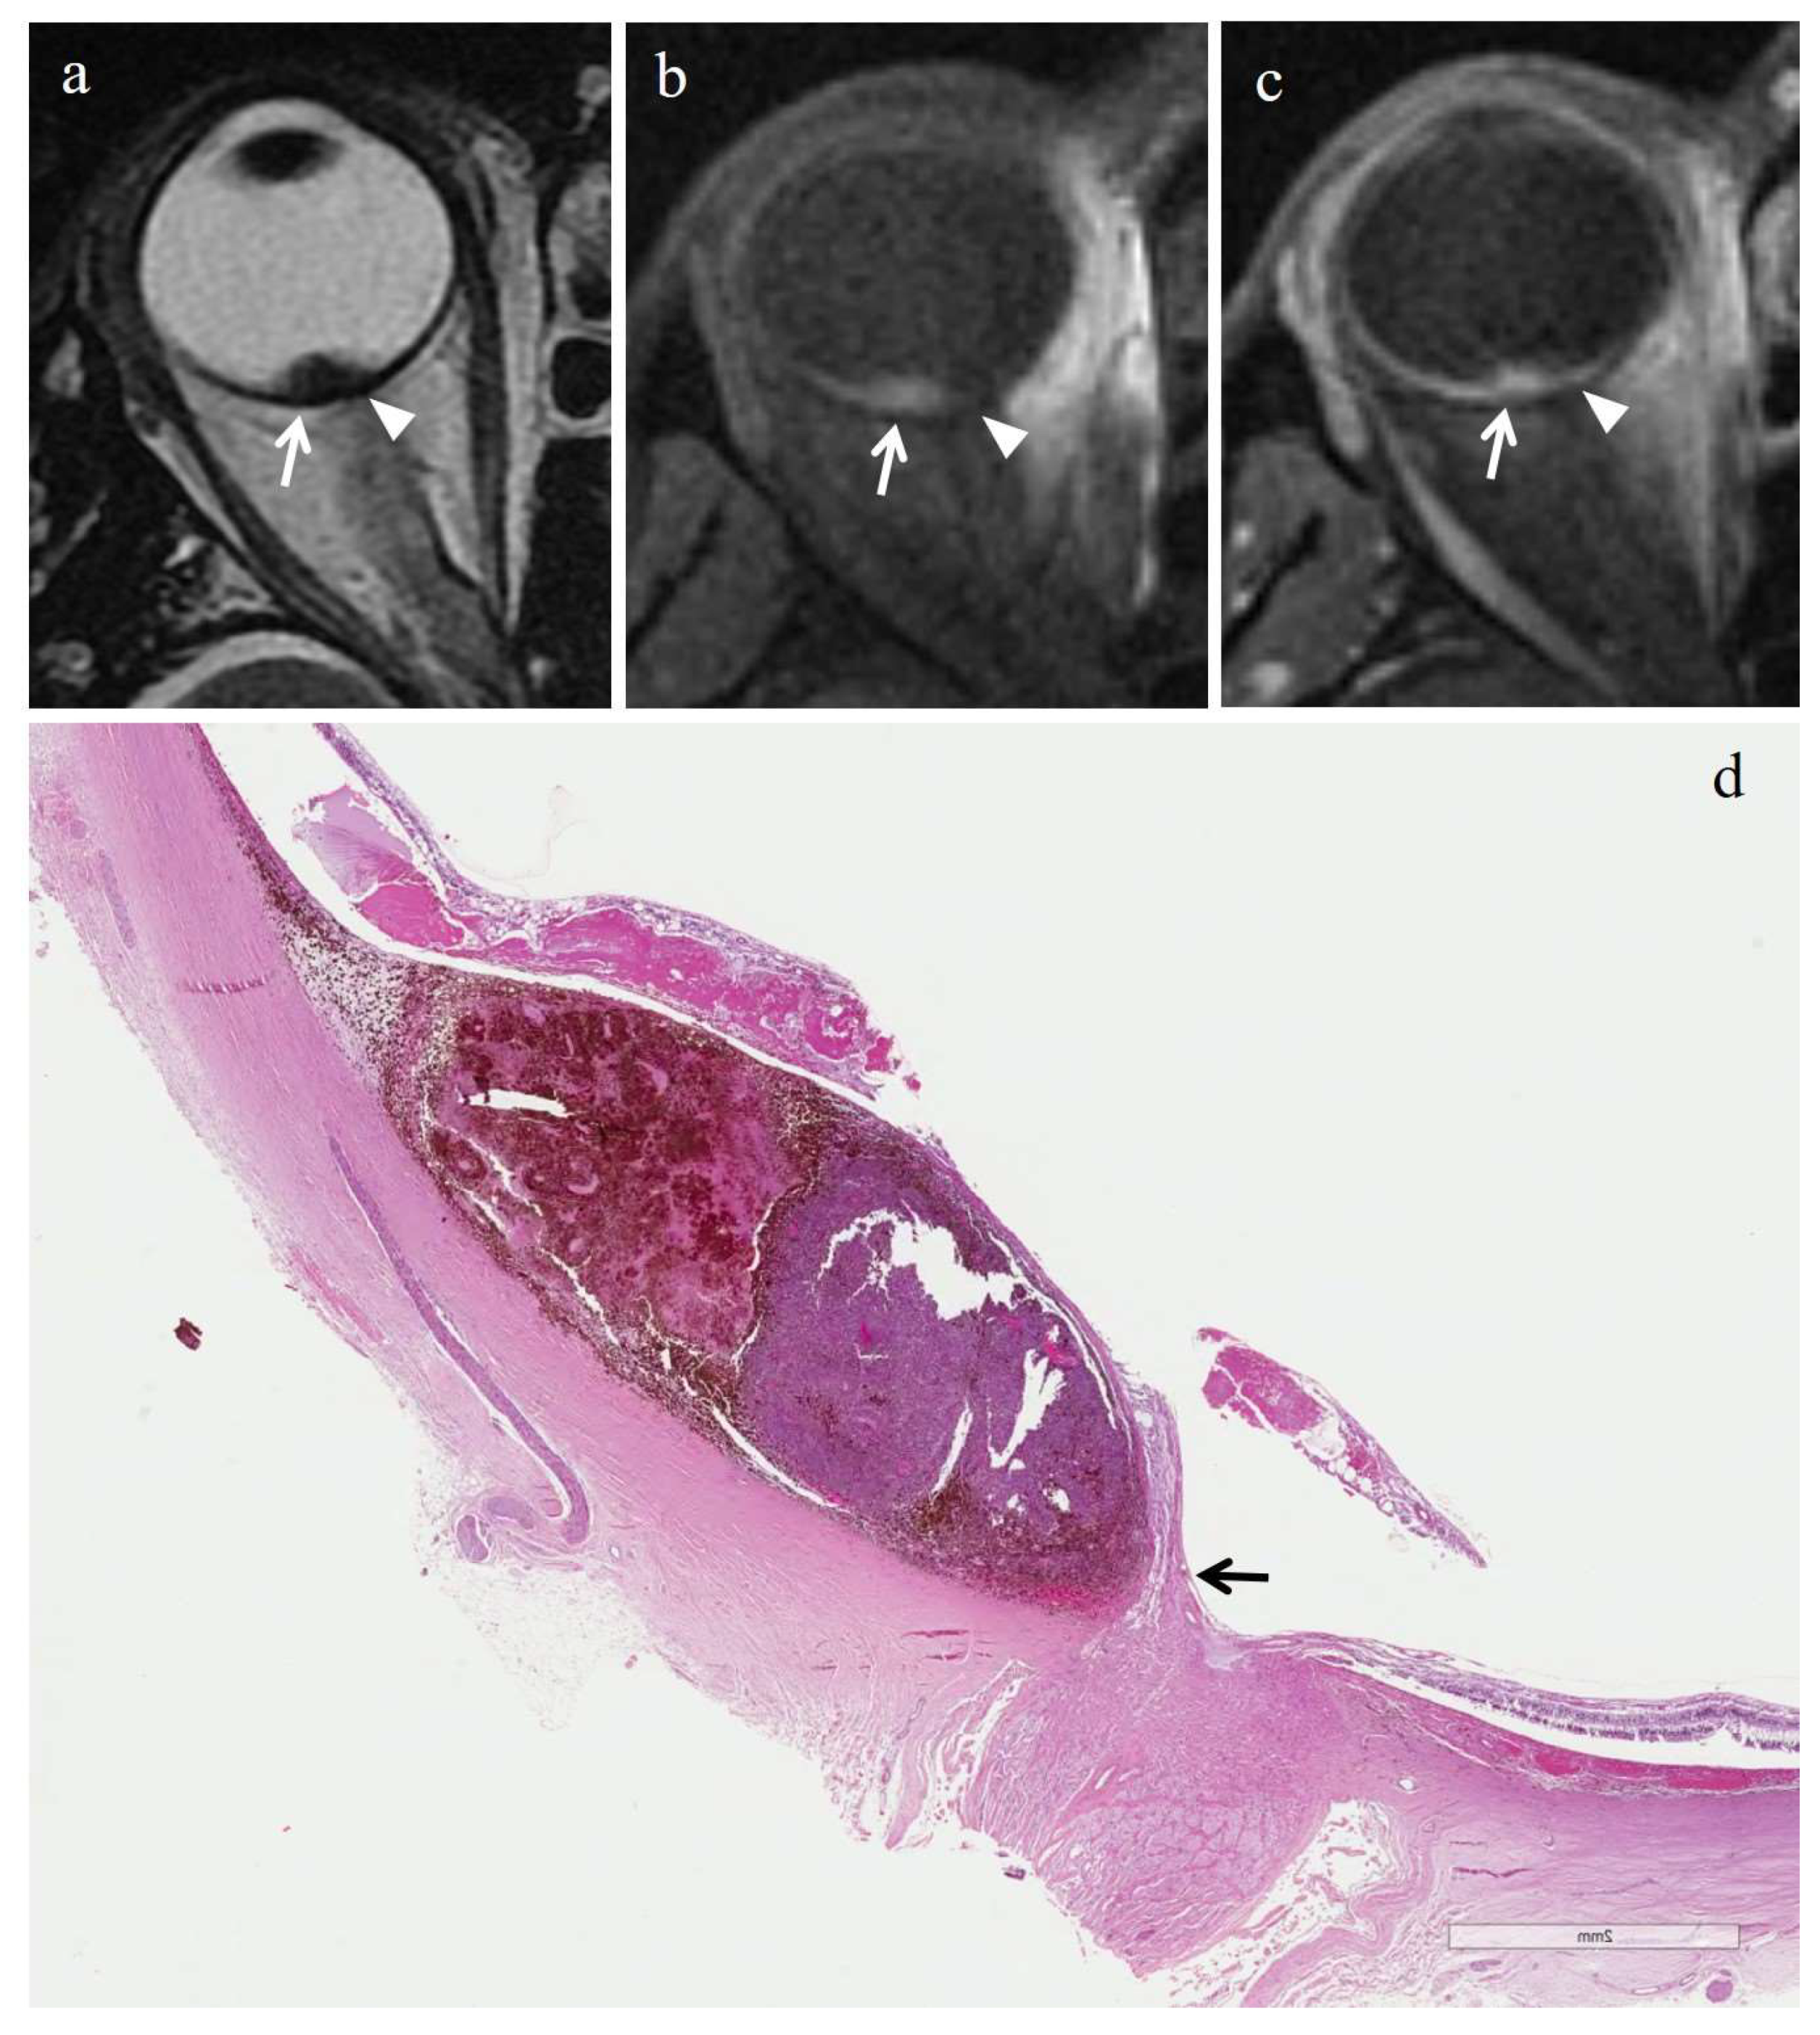

3.2.1. Histopathologic Findings in the Irradiated Group

3.3.1. MRI Findings in the Irradiated Group

| Patient | Histologic Type | Degree of Pigmentation | Degree of Necrosis | Necrotic Pattern |

|---|---|---|---|---|

| 1 | Necrosis without viable tumor tissue | - | Grade III | Sharply demarcated tumor necrosis |

| 2 | Spindle cell | Pigmented | Grade I | Sharply demarcated tumor necrosis |

| 3 | Epithelioid cell | Pigmented | Grade II | Sharply demarcated tumor necrosis |

| 4 | Spindle cell | Pigmented | Grade III | Sharply demarcated tumor necrosis |

| 5 | Mixed cell type | Poorly pigmented | Grade I | Multiple foci- hemorrhagic/coagulative-type |

| 6 | Mixed cell type | Poorly pigmented | Grade III | Sharply demarcated tumor necrosis |

| 7 | Spindle cell | Poorly pigmented | Grade III | Sharply demarcated tumor necrosis |

no enhancement; M: melanoma; RIN: radiation induced necrosis.| Patient | T2 | T1 | Gd-T1 | DWI | ADC × 10−3 mm2/s ** |

|---|---|---|---|---|---|

| 1 | Hypointense | Hyperintense | No enhancement | No restriction | - |

| 2 | - | - | - | - | 0.76 |

| 3 | Hypointense | Hyperintense | No enhancement | No restriction | 0.84 |

| 4 | Hypointense | Hyperintense | No enhancement | No restriction | - |

| 5 | Hyperintense | Hypointense | No enhancement | No restriction | 0.67 |

| 6 | Hypointense | Hyperintense | No enhancement | No restriction | - |

| 7 | Hypointense | Hyperintense | No enhancement | No restriction | 0.86 |